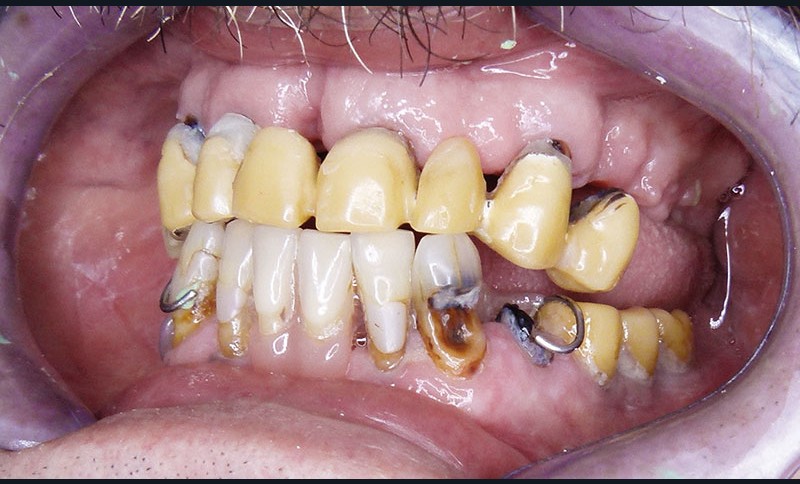

Monsieur L… se présente en décembre 2012 pour une demande de réhabilitation complète de sa cavité buccale. Il est âgé de 65 ans. Il présente un bon état de santé générale, sans pathologie restrictive. En revanche, son état bucco-dentaire est pour le moins problématique … Il est porteur de prothèses provisoires qui se sont délitées avec le temps. Plusieurs implants ont été mis en place auparavant, à la mandibule. Les restaurations d’usage n’avaient jamais été réalisées … (fig. 1 et 2).